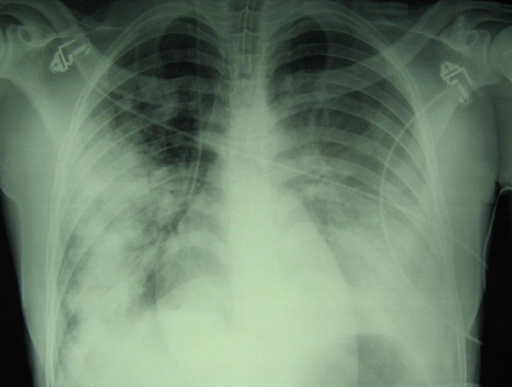

Die Bildgebung des Brustkorbs zeigt nun eine fast vollständige beidseitige Trübung der Lunge. Die Echokardiographie zeigt eine globale Hypokinesie, die im rechten Ventrikel stärker ausgeprägt ist, ohne Anzeichen einer Endokarditis.

ARDS_2.png

Brust-CT während des Aufenthalts auf der Intensivstation zeigt diffuse beidseitige milchglasartige Trübungen und Verdichtungen, die mit schwerem ARDS vereinbar sind.1